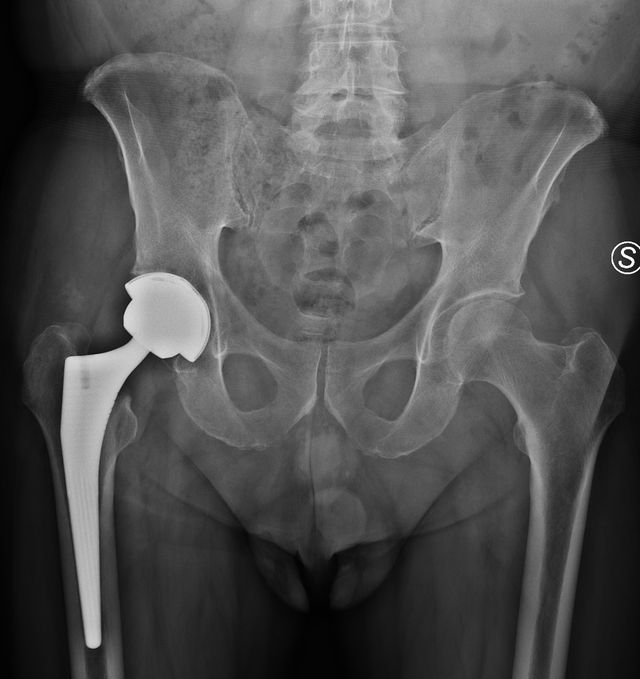

• Chirurgia Protesica Robotica e Tradizionale di Ginocchio e Anca: Interventi chirurgici di sostituzione articolare per il trattamento dell'artrosi.

• Chirurgia dell'anca